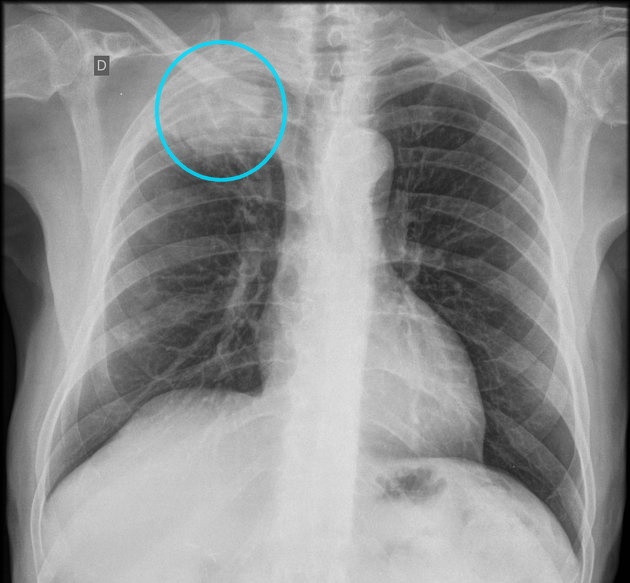

Puzzle 63

Puzzle 63 annotated